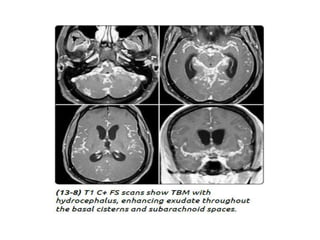

Tuberculous meningitis

• Tuberculous meningitis is the most common presentation

of intracranial tuberculosis, and usually refers to infection of

the leptomeninges.

• Tuberculous meningitis, although seen in all age groups, has a

peak incidence in childhood (particularly 0-4 years of age) in

high prevalence areas.